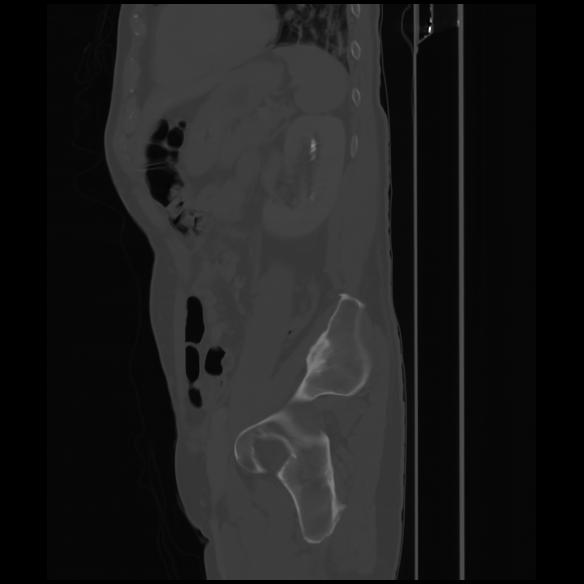

7 CUERPO,CE,Sagittal,3.000,CUERPO,Sagittal,